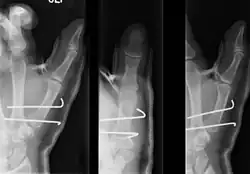

- For Bennett fractures where there is between 1 mm and 3 mm of displacement at the trapeziometacarpal joint, closed reduction and percutaneous pin fixation (CRPP) with Kirschner wires is often sufficient to ensure a satisfactory functional outcome. The wires are not employed to connect the two fracture fragments together, but rather to secure the first or second metacarpal to the trapezium.

- For Bennett fractures where there is more than 3 mm of displacement at the trapeziometacarpal joint, open reduction and internal fixation (ORIF) is typically recommended.

Regardless of which approach is employed (nonsurgical, CRPP, or ORIF), immobilization in a cast or thumb spica splint is required for four to six weeks.